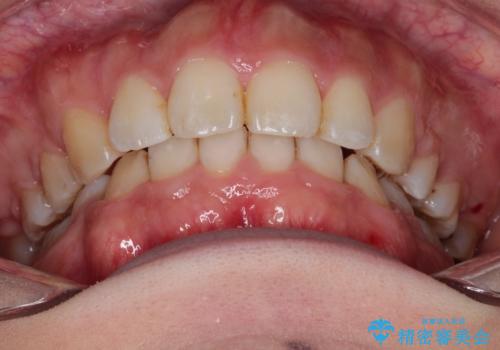

がたがたと出っ歯を直したい ワイヤーによる抜歯矯正

- ガタガタと出っ歯を主訴に来院されました。

上下左右の歯を1本ずつ、合計4本抜歯してワイヤーにて矯正治療をすることとなりました。

前から4番目の歯を抜歯することが多いのですが、右上の前から5番目の歯が神経の治療済みであり、こちらの歯を抜歯する計画としました。

通常より治療期間を要しましたが、健康な歯を残すことができました。